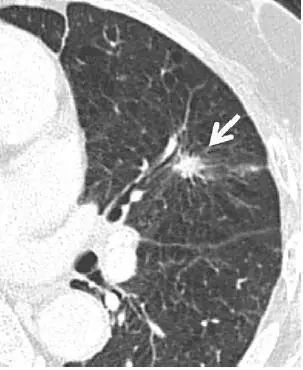

5、肺内淋巴结

图片

图 5 CT 图像,显示一个三角形实性胸膜下结节(箭头),且呈线状延伸至胸膜表面,为典型的肺内淋巴结表现,不建议 CT 随访。